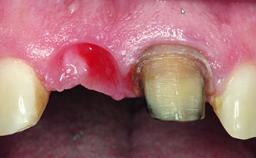

A 28-year-old patient presented at her general dentist’s office and complained about the appearance of her tooth 21. The patient had a history of trauma to this tooth. Endodontic treatment had been performed in the past and a crown placed on the tooth. A procedure to replace the old crown was performed by her dentist; however, a perforation on the middle third of the root occurred, and extraction of tooth 21 was suggested. Upon clinical and radiographic examination of the patient, who had been referred to us, replacement of tooth 21 by a dental implant appeared to be indicated.

Bone Volume Deficient horizontally, allowing simultaneous augumentation